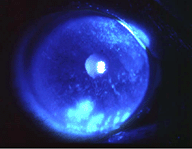

× [PR]上記の広告は3ヶ月以上新規記事投稿のないブログに表示されています。新しい記事を書く事で広告が消えます。 本日はブリスハウスの 内田 です(*^_^*) 先日より私は高度近視・・・という話題を出しておりますが、 今度はドライアイについてです。 最近目が乾くなあ。。。 というより 目が痛いなあ。。。 ゴロゴロするなあ・・・ という事が多く、 なんだろう なんだろう と思っていたらこれは ドライアイ だそうです ![]() 目が乾いて角膜に傷がついて痛みを感じるそうです。 これには、涙点プラグと使うのがいいそうです ![]() ![]() 涙点プラグ挿入術は、外来による簡単な処置で行えます。 まず、点眼麻酔をし、患者さんの涙点の大きさを測定し、 挿入するプラグのサイズを決定します。 プラグの挿入は、ペンのような専用の道具を使いワンタッチで施行できます。 痛みはなく、5分程度で終了します。 涙点プラグは、一度挿入しても、外来ですぐに外すことができます。 ↑ これ、やってみようかなー ![]() とおもっている今日この頃です ![]() 皆さんも眼はお大事に!! C21ブリスハウスホームページはこちら![]() http://www.blisshouse.co.jp C21リリーストホームページはこちら http://www.released.co.jp PR おはようございます。